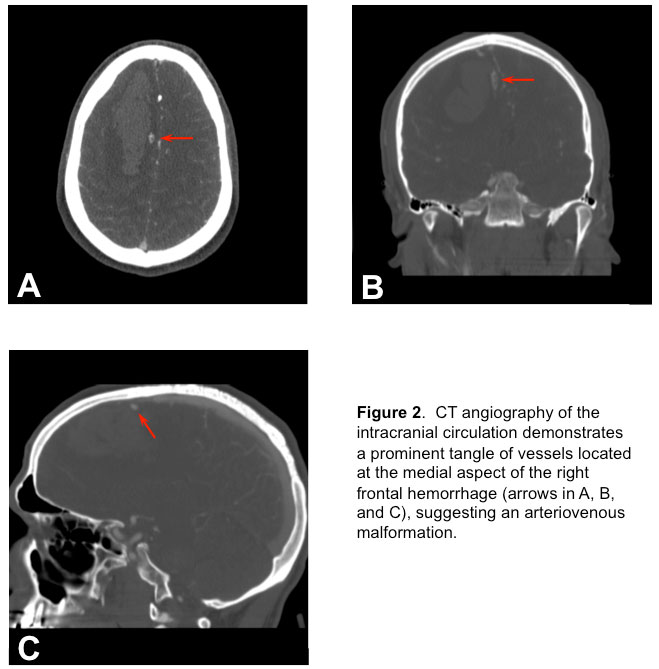

and a CT angiography (CTA) of the brain (Figure 2)

revealed an arterio-venous malformation (AVM). Soon after presentation, he became more lethargic with episodes of bradycardia to the 30s and without concomitant hypertension. He was subsequently intubated for airway protection with propofol and rocuronium. In addition, 50 grams of mannitol was administered intravenously due to concerns of rising intracranial pressure (ICP). Now intubated, propofol infusion was titrated to maintain deep sedation (no response to painful stimuli). He was then moved to the neurointensive care unit (NSICU).

2) Brain CTA showed the appearance of an apparent AVM supplied by the anterior cerebral arteries with superficial drainage at the superior sagittal sinus.